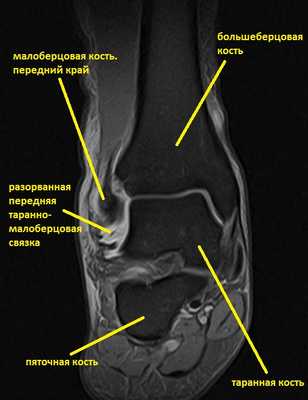

Ниже представлены срезы МРТ в которых наглядно показано расположение повреждённых связочных структур.

Данные повреждения практически в 100 % случаев пропускаются при первичном обращении в травмпункт. При несвоевременном или неадекватном лечении нестабильность голеностопного сустава приводит к разрушению суставного хряща, выраженной боли, деформации, и в конечном счёте к полной утрате функции опоры и ходьбы. В зависимости от того какие связки разорваны и от того насколько выражена нестабильность, артроз развивается в разные сроки, от 1 года при разрыве синдесмоза, до 20 и более лет при изолированном разрыве передней таранно-малоберцовой связки.